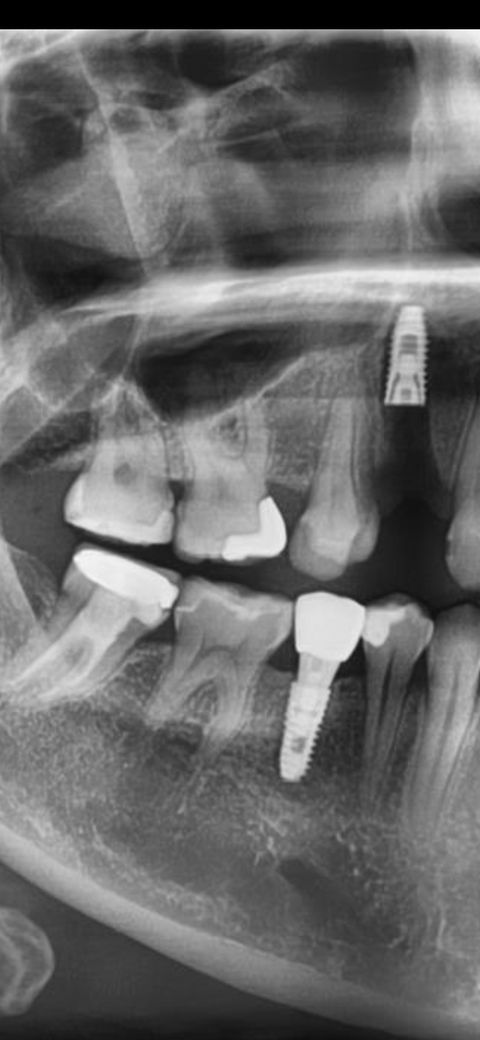

다니던치과 사기당해서 다른치과가서 임플란트해야하는데 잘 된게맞나요? 지주대 머리 연결하기전 나사만 박혀있습니다ㅠㅠ하 골아프네요 정말

사진으로만 봤을 경우에는 임플란트의 뿌리가 매우 깊게 식립된것으로 보입니다.

이런경우 보철물을 제작할때 지대주의 길이가 매우 길어질수 있을것으로 생각됩니다.

사진으로 보아 정상적으로 심어진 것으로 보입니다. 본인이 느끼는 통증이나 불편감 없다면 성공적으로 심었다고 보면 됩니다.

임플란트가 깊게 심겻긴하지만 크게 문제가 잇어 보이진 않는거 같습니다. 기다리셧다면 보철물을 올리시면될것같습니다.

솔직히 말씀드리자면 너무 깊습니다. 너무 깊어서 제거하기도 쉽지 않고 보철물을 어떻게든 만들어볼수도 있겠습니다만 기계적으로나 위생적으로 좋지는 않습니다.

저 사진만 봐서는 정확히 평가는 어렵고요 잇몸뼈가 깊이가 부족하여 뼈가 있는쪽으로 다소 깊게 의도적으로 심은 것 같습니다 앞으로 뼈와 픽스처가 잘 유착되기만을 기다리면 됩니다